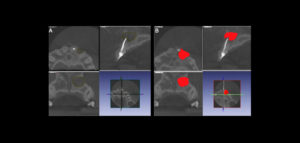

Se sabe que la tomografía computarizada de haz cónico (CBCT) produce exploraciones tridimensionales de la dentición, las estructuras duras maxilofaciales y la relación de las